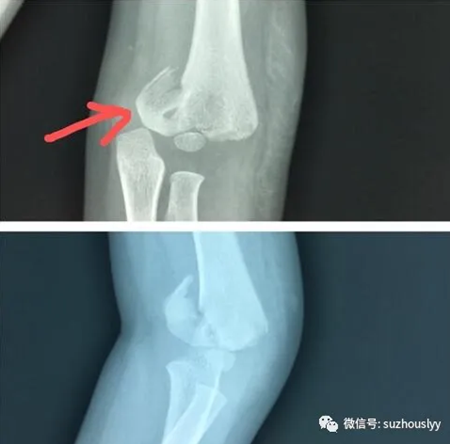

车祸伤致胳膊肘骨折明显移位

急诊送至我院儿童重症医学科监护室,诊断“双肺挫伤、肝破裂、腹部损伤、左上肢骨折、失血性休克、水电解质紊乱、头部外伤、全身大面积皮肤挫裂伤”。在主任杨林风、主治医师刘祥蕾、医师闵波杰及全体医护的及时、精心救治下,脱离生命危险。伤后10天,可心病情相对稳定后,转入我院骨一科(儿童骨科治疗组)。